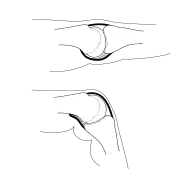

MCP joint in extension and in flexion, palmar plate in grey | |

This fibrocartilaginous structure is attached to the volar base of the phalanx distal to the joint. From there, it forms a palmar continuation of the articular surface of the phalanx bone and its inner surface thus adds to the articular surface during extension. [2]

In its proximal end, the volar plate becomes membranous and blends with the volar capsule which is attached to the head of the metacarpal bone. During flexion, the plate glides proximally down the volar surface of the metacarpal head. Its flexible attachment to the phalanx bone not only prevents it from restricting joint movements, but also prevents the long flexor tendons from being pinched in the joint. [2] Flexion of the proximal phalanx is facilitated by the shape of the proximal edge, known as the volar recess,[5] but this diaphanous end of the volar plate is also the part of the metacarpophalangeal joint that is most susceptible to injury during dislocations.[6]